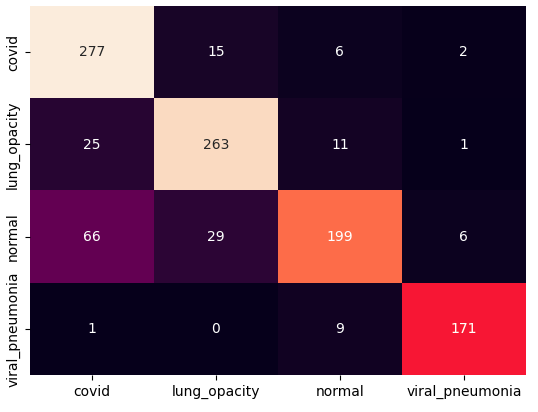

The training procedure in all scenarios has converged. Looking at the evolution of training and validation accuracy (Fig. 11a) indicates that a larger validation dataset would be beneficial. To stabilise the classifier training a procedure of multiple training runs to select the best model is used (Materials and methods). Resulting classifiers are able to discriminate between classes with good precision, for example, see the confusion matrix of the best overall model presented in Fig. 11b. It can also be seen that for the normal class, the rate of misclassified images as COVID-19 ones is higher than for other classes. This effect is present for all models although smaller for the ones based on the EfficientNet-B0 architecture. In addition, the EfficientNet-B0 variants excel if the correct classification of viral pneumonia class images with the smallest rate of errors. However, the EfficientNet-B0 GAN augmentation scenario shows increased misclassification of healthy images which leads to a poor performance. The evolution of the training accuracy as well as confusion matrices for all models are summarised at the end of this section.

Training results for the two architectures are summarised in Figs. 13, 14, 15, 16, and Table 3. For each architecture four scenarios are considered as described in Training process part of the Materials and methods Section.